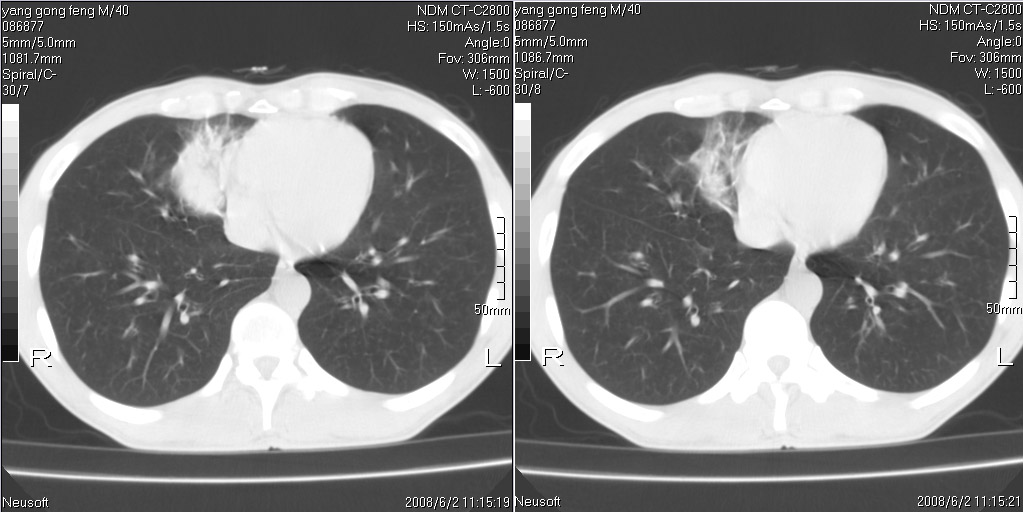

标题: CT15138:男,40,咳嗽胸痛. [打印本页]

标题: CT15138:男,40,咳嗽胸痛.

外院穿刺未见癌细泡,结核菌素实验阳性,未正规治疗2个月复查病灶及纵隔淋巴结增大

考虑周围型肺癌可能性大

考虑右肺中叶周围型肺癌并纵隔淋巴结转移。

考虑周围型肺癌伴纵膈淋巴结转移可能性大

强化看看吧,有助诊断的